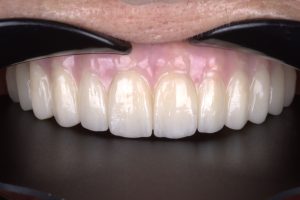

Case: Buccaly Displaced Flap

Initial state – Patient lost central incisor some time ago Intraoral Scan – clearly visible…